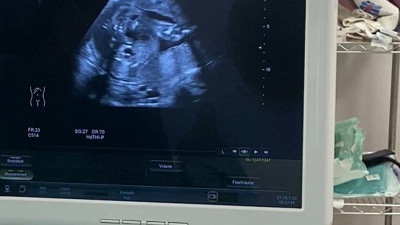

Anne karnındaki bebeğe mucize müdahale Elazığ’da anne karnında idrar çıkış yolu darlığı tespit edilen bebeğe stent takılarak idrarını yapması sağlandığı bildirildi.